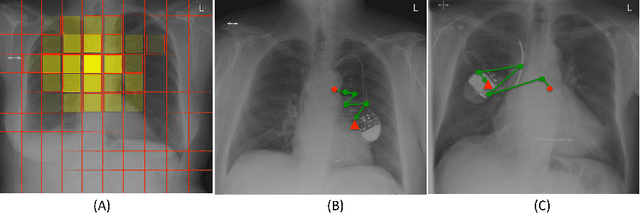

Abstract:X-rays are commonly performed imaging tests that use small amounts of radiation to produce pictures of the organs, tissues, and bones of the body. X-rays of the chest are used to detect abnormalities or diseases of the airways, blood vessels, bones, heart, and lungs. In this work we present a stochastic attention-based model that is capable of learning what regions within a chest X-ray scan should be visually explored in order to conclude that the scan contains a specific radiological abnormality. The proposed model is a recurrent neural network (RNN) that learns to sequentially sample the entire X-ray and focus only on informative areas that are likely to contain the relevant information. We report on experiments carried out with more than $100,000$ X-rays containing enlarged hearts or medical devices. The model has been trained using reinforcement learning methods to learn task-specific policies.